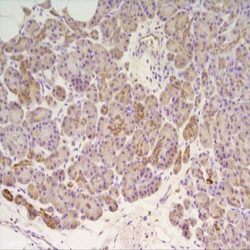

| Dilution | 1:50 |

| Staining | Cytoplasm |

| Control tissue | Tissue section from chromophobe carcinoma of the kidney |